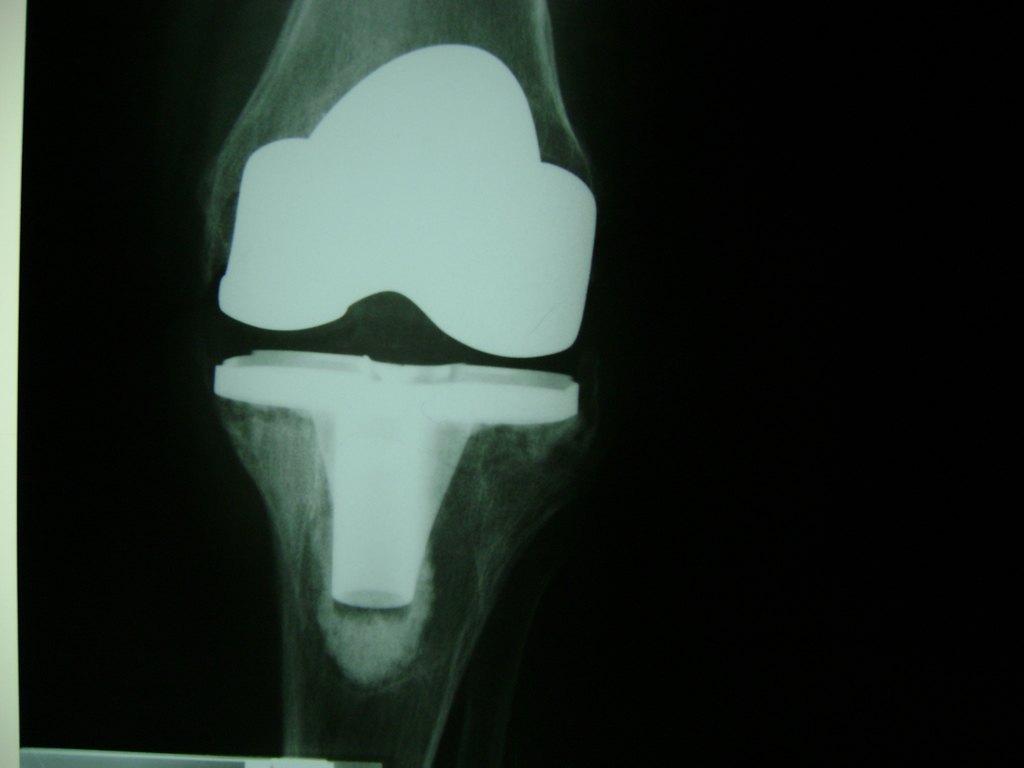

Cirugías de Codos - Rodilla

La artroscopia de rodilla es un cirugía en el cual la estructura interna de la articulación es examinada ya sea para realizar un diagnostico o para realizar un tratamiento, este procedimiento se realiza utilizando un instrumento parecido a un pequeño tubo llamado artroscopio.